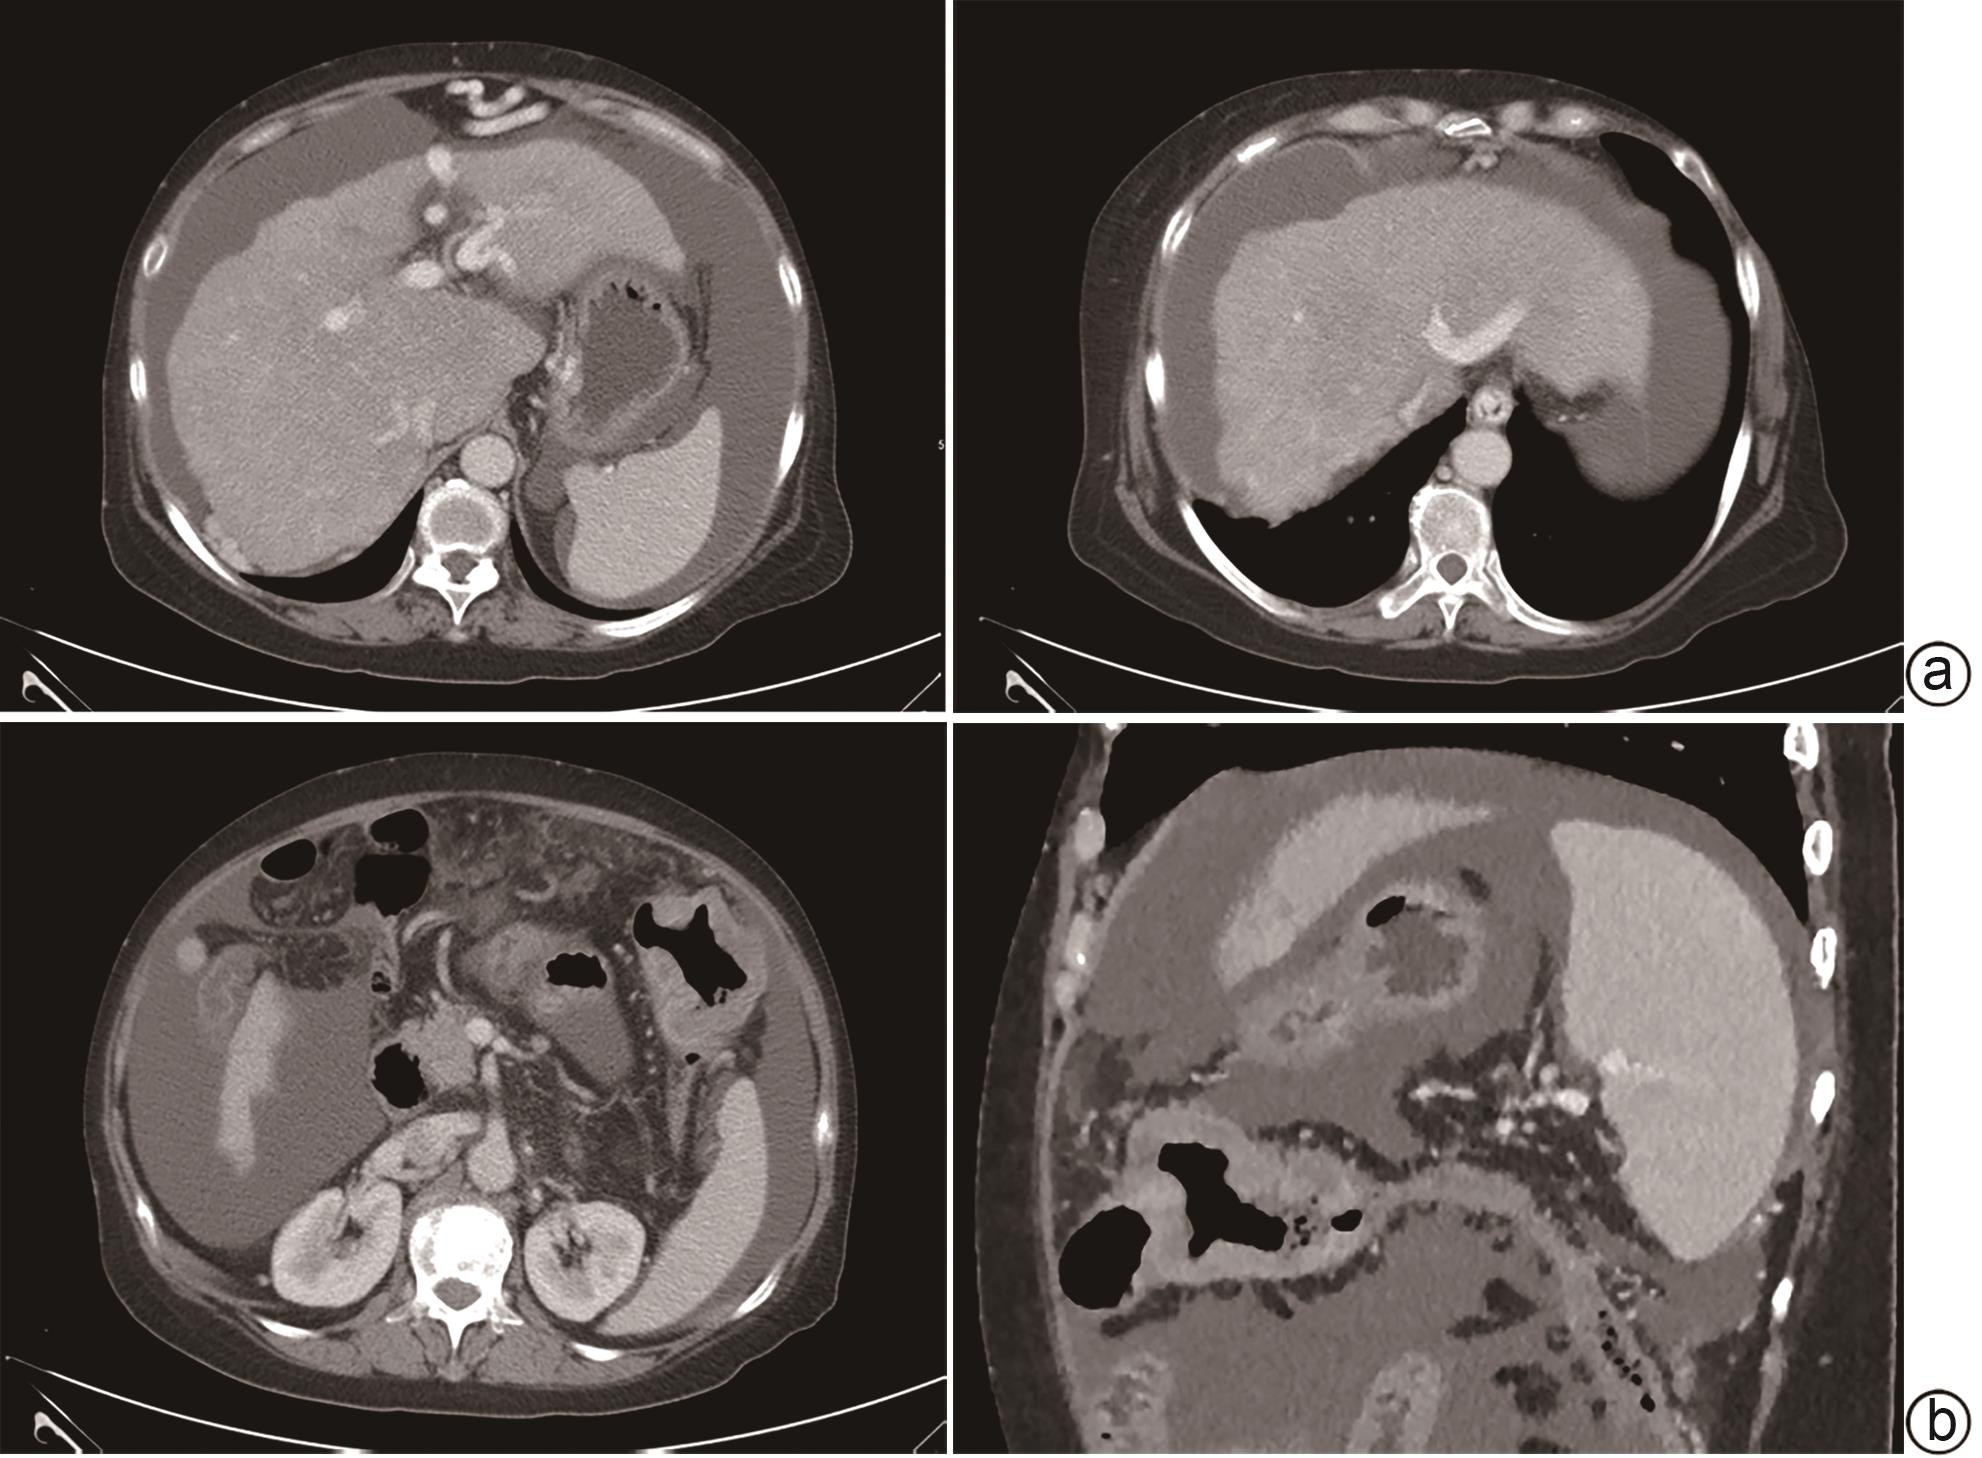

术前ALT/AST联合多期CT影像学指标对胰十二指肠切除术后临床相关胰瘘的预测价值

潘均昊, 辛建, 王春晖

2024, 40(9): 1859-1867. DOI: 10.12449/JCH240922

摘要(834) HTML (359) PDF (2208KB)(47)

摘要:

目的  探讨胰十二指肠切除术后发生临床相关胰瘘(CR-POPF)的危险因素,并建立预测模型,对CR-POPF患者进行早期预测。  方法  选取北部战区总医院2019年1月—2023年10月244例行胰十二指肠切除术的患者,经过严格的纳入排除标准筛选后最终纳入179例患者,根据是否发生CR-POPF分为非CR-POPF组(n=120)和CR-POPF组(n=59)。采用单因素和多因素Logistic回归分析确定CR-POPF相关的独立危险因素,并构建列线图。采用受试者工作特征曲线评价预测效果,校准曲线评价模型校准度,用临床决策曲线和临床影响曲线分析验证模型的临床应用价值。计数资料组间比较采用χ2检验或Fisher精确概率法;计量资料符合正态分布的2组间比较采用成组t检验,偏态分布的2组间比较采用Mann-Whitney U检验。  结果  179例患者中59例发生CR-POPF,发生率为33.0%。经过多因素Logistic分析确定术后CR-POPF的独立危险因素:较大的ALT/AST(OR=2.221,P=0.004)、主胰管直径≤3 mm(OR=0.276,P=0.022)、较大的腹膜胰颈前距离(OR=1.034,P=0.027)、较小的细胞外体积分数(OR=0.001,P=0.005)。根据上述4个独立危险因素构建预测胰十二指肠术后CR-POPF的列线图,该模型的受试者工作特征曲线下面积为0.837,敏感度为0.932,特异度为0.725。决策曲线和影响曲线的结果也显示该列线图具有良好的临床实用性。  结论  术前临床指标联合多期CT共同预测胰十二指肠切除术后CR-POPF的模型效能良好,可以在术前对胰瘘高危患者进行早期识别,进一步指导临床工作。